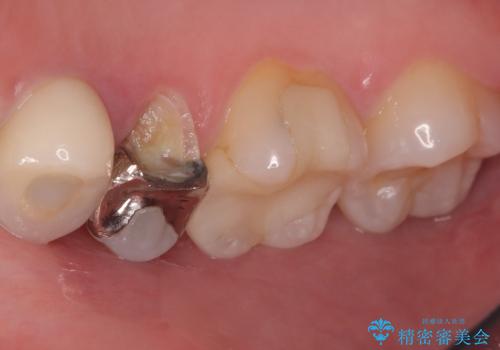

- 主訴:銀の詰め物を入れている歯が割れてしまった。

右上5番に保険適応のインレーが入っている歯がインレーを境に2つに割れてしまっていました。

右上5番の口蓋側歯質が失われ、露出した歯質内面は軟化象牙質を除去していく過程で露髄する可能性が大きくありました。患者さんには生活歯髄療法と抜髄のどちらかになると説明し、生活歯髄療法の適応と判断し行いました。